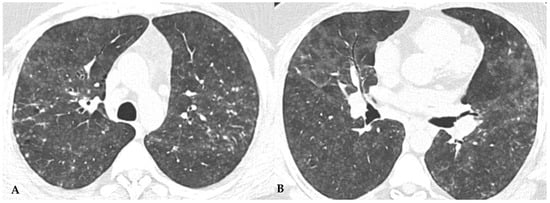

Due to intrinsic limitations in spatial resolution and contrast, chest X-rays are ineffective in evaluating NFHP, as they may appear normal or demonstrate nonspecific reticular changes in advanced forms. In cases of clinical suspicion, HRCT is considered the gold standard for detecting HP-related alterations. A rigorous methodological approach is required for HRCT to enhance mosaic attenuation areas, which can be accurately diagnosed as “air trapping” in expiratory scans, with a well-known algorithm in the literature: 1/1.25 mm thickness, specific high-resolution convolution kernels and reconstruction filters (bone filters added to soft tissue filters for accurate mediastinal evaluation and assessment of additional ancillary findings) and volumetric acquisition in the inspiratory and expiratory phases (low dose, if necessary). This evaluation plays a key role in diagnosing HP and identifying components that can affect the lungs differently, with heterogeneous characteristics of aggressiveness. Common findings in NFHP reflect inflammation that initially affects small airways with a “bronchiole-centric” type of tropism, analogous to histopathological findings. Lymphoplasmacytic infiltrates (cellular bronchiolitis) with a “fluffy” appearance, leading to the formation of hazy GGO, are often present (Figure 1A,B), along with the production of non-necrotizing granulomas in bronchiolar and peri-bronchiolar locations (Figure 1C,D).

NFHP: axial chest HRCT scan (A,B): 38-year-old male exposed to molds, inorganic cement dust and glass resin with exertional dyspnea and dry cough: numerous centrilobular “fluffy” nodules with a rosette appearance, suggestive of an acute and non-fibrotic form of hypersensitivity pneumonitis, are observed in both upper lobes and apical segments of the lower lobes. In (C,D): NFHP: The pathological views after cryo-biopsy (same case (A,B)) showed airway-centered changes with peribronchiolar damage ((C): hem-eo 40×), with interstitial cellular infiltration, poorly formed non-necrotizing granulomas (black arrow) and interstitial giant cells ((D): hem. eo 20×). In addition to these findings, areas of GGO may coexist, simulating exudative phases of diffuse alveolar damage (Acute Interstitial Pneumonia, AIP) in the acute phase, along with areas of different lung attenuation called mosaic attenuation (HRCT in inspiration) and air trapping (HRCT in expiration) with “lobular and/or geometric” morphology, indicating acute obstructive damage to small airways (Figure 2).

Ancillary findings such as smooth septal thickening and/or pleural effusion may also coexist with typical findings. The presence of numerous inflamed lymph nodes is often described. Another typical finding in the past described as the “head cheese pattern”, now described as “the three-density pattern”, was correlated with the combination of GGO opacities, integrated into a context of air trapping and normal lung. The clear lung heterogeneity, sometimes definitively recognizable in HRCT evaluations, is very suggestive and sometimes pathognomonic of HP in multiplanar reconstructions (Figure 2). Radiological features of HP are influenced by the histopathological stage of the disease at the time of diagnosis. According to international guidelines about HRCT features, HP (both the fibrotic and non-fibrotic forms) can be classified into “Typical HP”, “Compatible with HP” and “Indeterminate for HP”, each presenting typical, compatible or “not-specific” radiological and pathological elements, respectively. HRCT is a pivotal examination for diagnostic confirmation after a comprehensive clinical assessment, functional tests and BAL, with or without transbronchial biopsy (if deemed necessary by the clinician). It is also essential for the ongoing diagnostic process in the follow-up of patients with confirmed diagnoses through a MDT approach, providing information on therapeutic response and defining the possible progression of damage toward fibrotic transition as additional prognostic information useful for evaluating a different therapeutic approach (antifibrotic therapy). The distinctive feature of fibrotic HP is the coexistence of pulmonary fibrosis, often with signs of bronchial obstruction. In fibrotic HP, fibrosis more frequently appears as irregular and coarse reticulation associated with architectural distortion and septal thickening, which may be accompanied by bronchiectasis and bronchioloectasis that is more evident in ground-glass areas (Figure 3), with a centrifugal distribution (broncho-centric) and extension along the bronchovascular axis. These semiotic characteristics significantly differ from the fine and delicate reticulation observed in IPF, reflecting the intrinsic characteristics of immune-mediated inflammatory damage [7,8].

NFHP: chest HRCT ((A,B): axial scan; C: MPR coronal). GGO pattern and faint centrilobular nodules are observed in both upper lobes and apical segments of the lower lobes (A,B). Areas of mosaic attenuation (black arrows) are better defined in the coronal MPR reconstruction (C). The pattern is suggestive of an acute, non-fibrotic expression of hypersensitivity pneumonitis (NFHP).